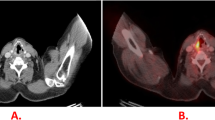

Concordant FDG-PET and CT findings in a 52-year-old woman with centrally located SCLC and a pretracheal lymph node metastasis. a FDG-PET demonstrates high FDG uptake in a large lesion in the right lung and right pulmonary hilus. Furthermore, FDG-PET shows a pretracheal hot spot on the right side. Physiological FDG uptake in the urinary tract is also apparent. b A representative axial CT scan confirms the pretracheal lymph node metastasis and c shows that the tumour mass is infiltrating the mediastinum and surrounding the trachea and oesophagus